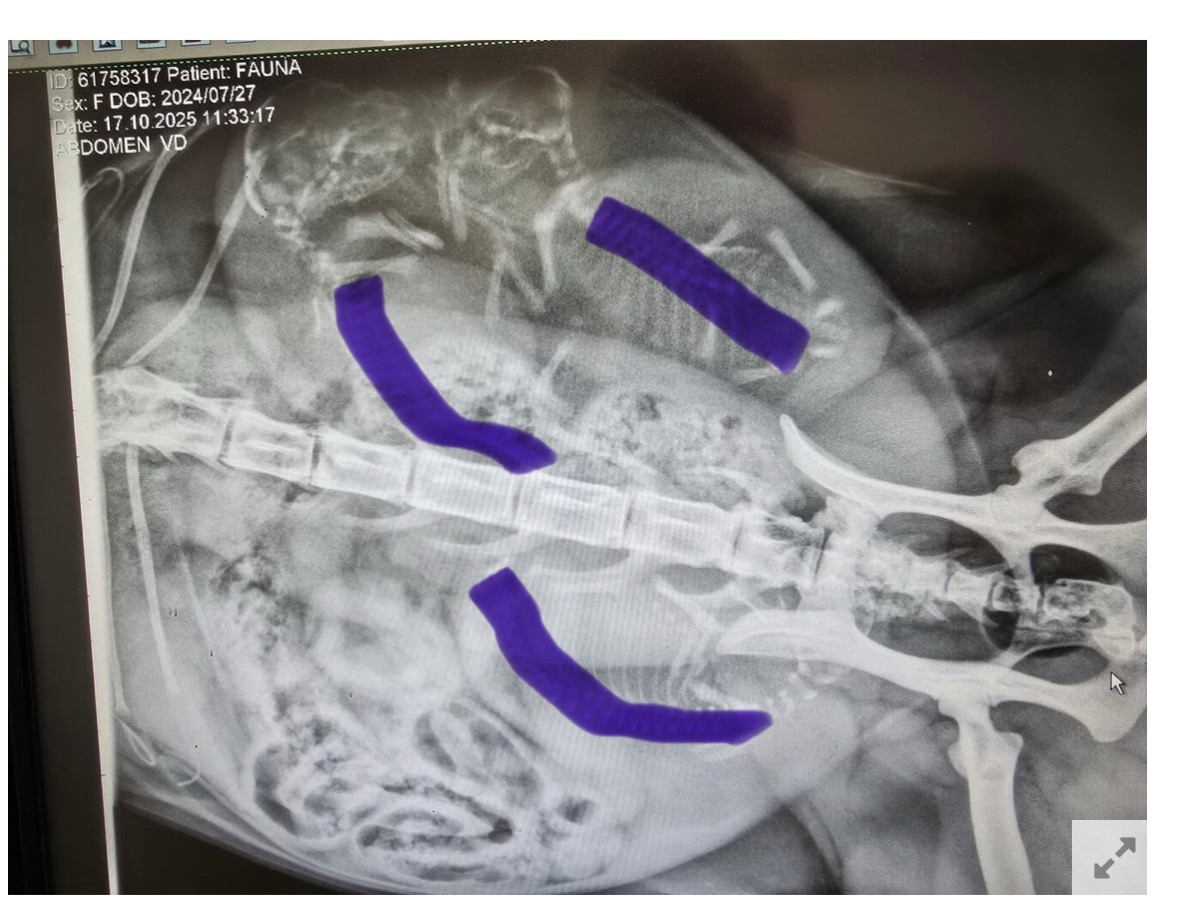

Så har vi været en tur forbi dyrlægen og fået taget røngten.

Hvor mange kan i tælle ??

Der er rygrad, hvor de blå markeringer er :slightly_smiling_face:

Jeps der er 3 styk og som _DK_Sugieh skriver, så kigger man efter rygsøjler og ser om der er samme antal hoveder, så er man sikker på at have talt rigtig.

Jeg tror det er et fint antal til hende, hun er trods alt kun 1 år og 3 måneder, så er forholds vis ung mor